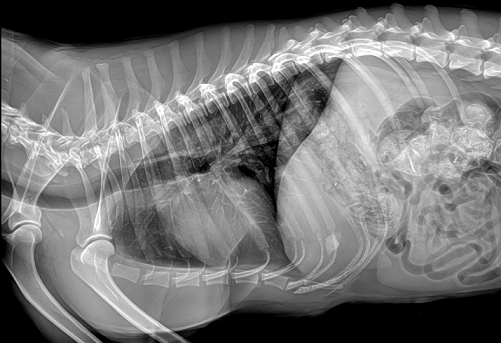

國產品牌普愛醫(yī)療寵物dr采用非晶硅平板探測器,可以令動物影像成像清晰而快速,基本上5s左右就能使動物影像清楚成像且無拖尾現(xiàn)象,而且分辨率高,極限空間分辨率可達到5.0Lp/mm;

普愛醫(yī)療寵物dr拍攝的高清照片

同時,寵物影像成像尺寸較大,成像尺寸可達43cm x 43cm,并且以DICOM格式儲存數據,極大的方便了醫(yī)療工作者們追蹤檢查時使用。同時還支持窗寬、窗位、放大、旋轉、正像和負像轉換等顯示功能。如果您想購買普愛醫(yī)療寵物dr,或了解具體技術參數,歡迎聯(lián)系我們。